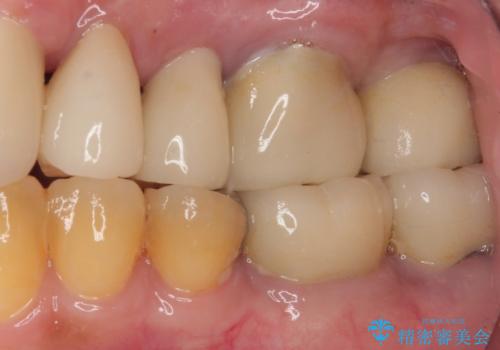

破折によりクラウンの外れてしまった奥歯 抜歯即時埋入で短期間インプラント治療

- 奥歯に装着していたクラウンが外れてしまったとのことで来院された患者様です。

診察したところ、歯根に破折線が確認され抜歯が必要な状態でした。

歯肉や歯槽骨の状態は良好であったため、抜歯即時埋入インプラントによる補綴治療を行うこととしました。

最小の来院回数で短期間で治療を終えることができました。